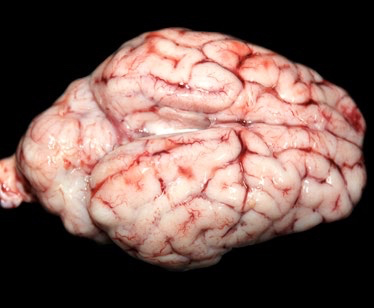

Streptococcus suis: claves diagnósticas desde la lesión hasta el laboratorio